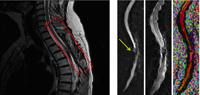

NOTR.png